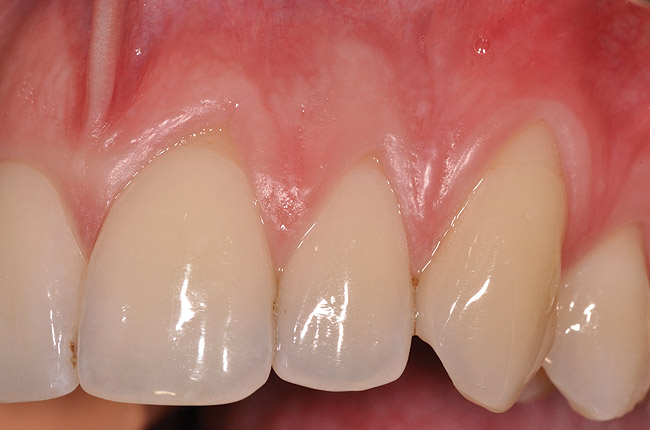

Fig 14. One-year postoperative view of case presented.

Figure 14

Once the flap was coronally repositioned and secured, a securing periosteal tac procedure was performed to prevent any micro movement superior to the mucogingival junction in the initial healing phase. A 4.0 chromic gut suture (Surgical Specialties Corp.) was used to engage the periosteum superior to the mucogingival junction and stabilize the tissues superior to the securing suture (Figure 12 and Figure 13). Multiple periosteal tac sutures may be necessary, depending on the size of the surgical field. Postoperatively, the periosteal tac sutures are routinely removed if not totally absorbed at 7 days; the flap sutures are removed at 2 to 3 weeks, and dermal-securing sutures are removed 1 month after surgery. The 1-year post-treatment clinical view shown in Figure 14 depicts the excellent soft-tissue result, band of attached keratinized tissue present, and excellent color match to the host gingival tissues.